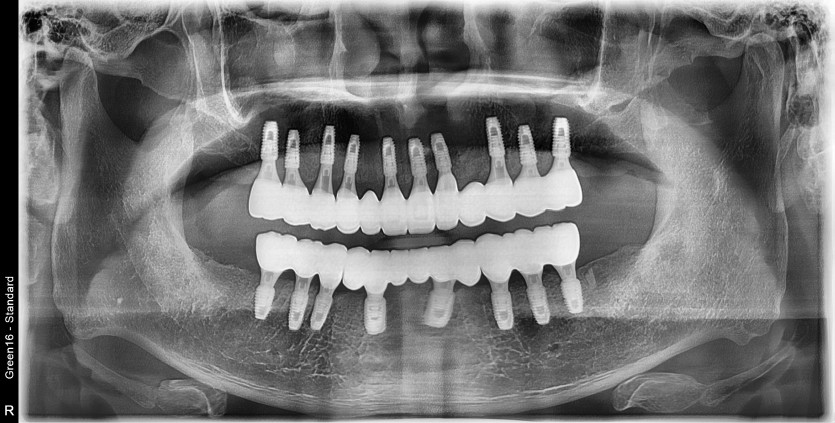

만 53세 전체 임플란트 증례

전체 임플란트 증례입니다.

18개의 임플란트로 완성하였습니다.